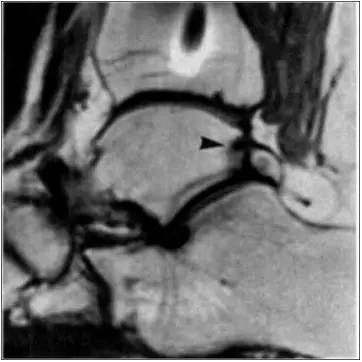

- MRI 检查示距后三角骨及周围软组织有水肿信号,距后三角骨和距骨之间正常的低信号纤维连接中断,出现液性信号。

3、MR表现:

- 三角籽骨或距骨后三角结构模糊和变形,T1WI信号降低, T2WI信号升高,

- 周围脂肪水肿,

- 踇趾长屈肌腱信号升高,见鞘膜积液,

- 胫骨后下跟骨上缘骨结构形态变化和信号异常,

- 三角籽骨和距骨退行性囊变。

三角籽骨综合征

三角籽骨综合征并跟腱滑囊积液